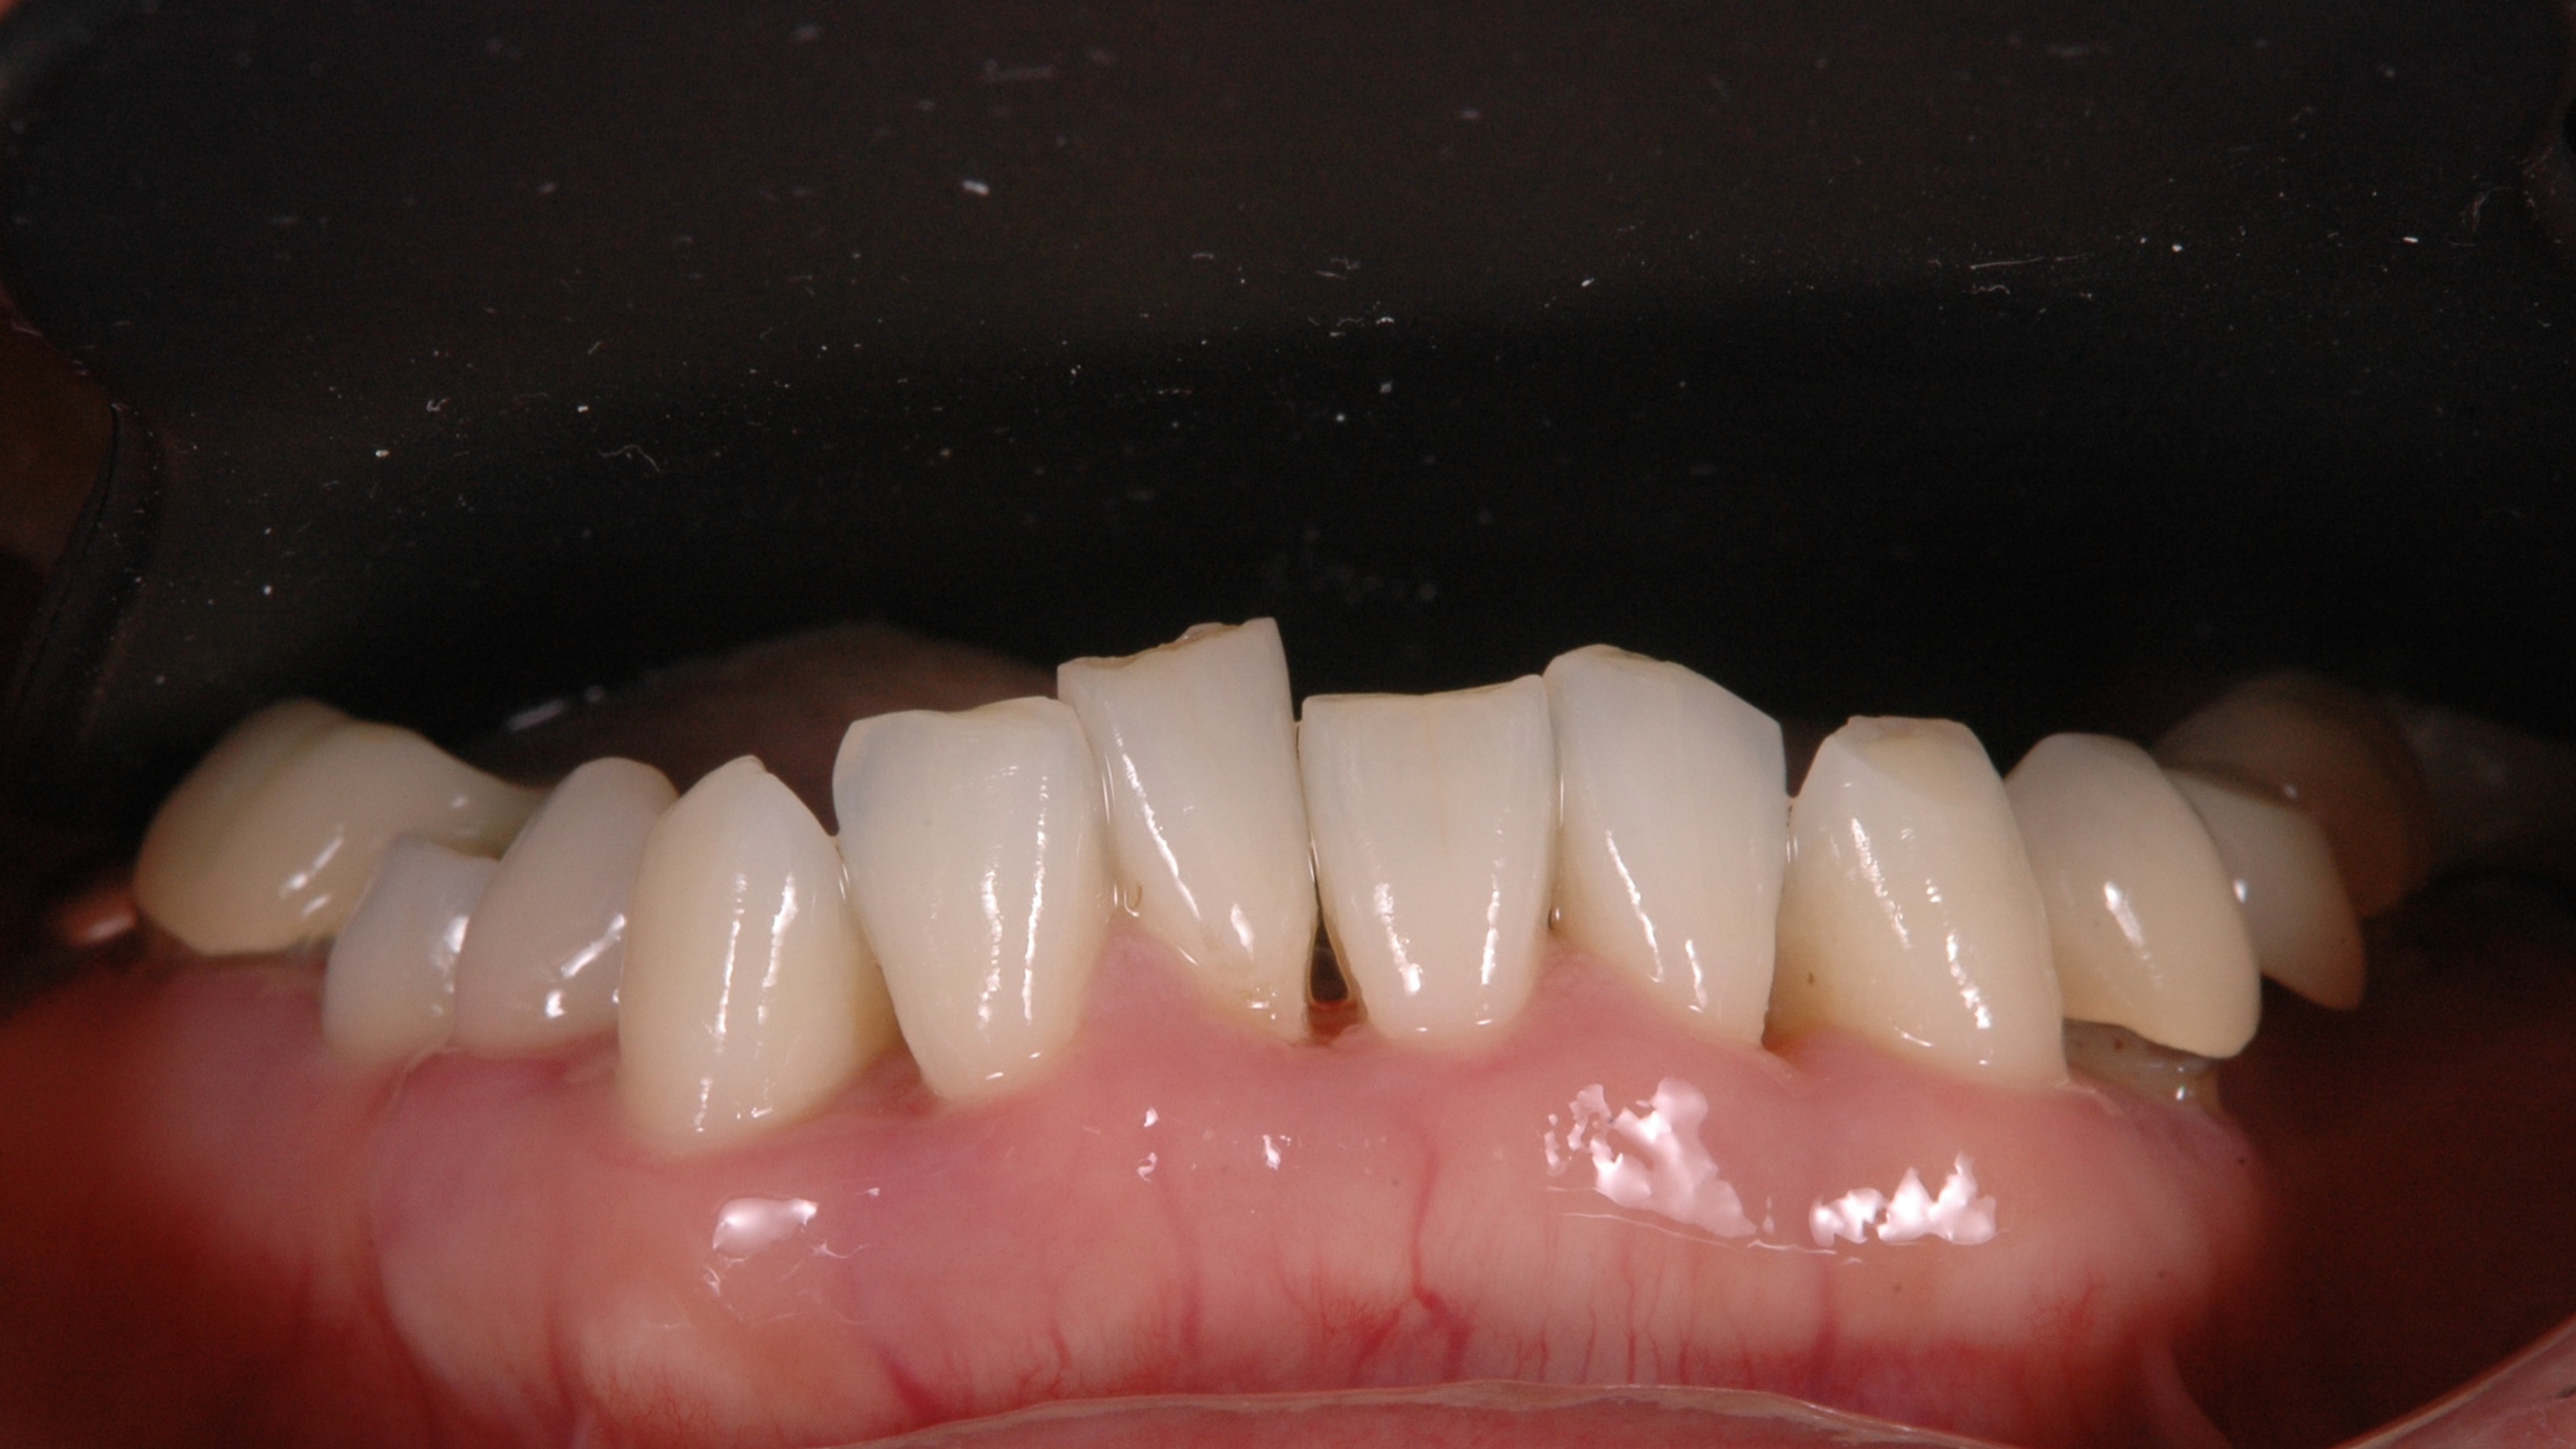

歯周病 2018.12.27 グラグラな歯、進行した歯周病、抜かずに治せる?PART2 進行した(中等度-重度)歯周病,歯槽膿漏の治療は様々! 上の写真は全体的に中等度から重度に進んだ歯周病患者さんの歯石...